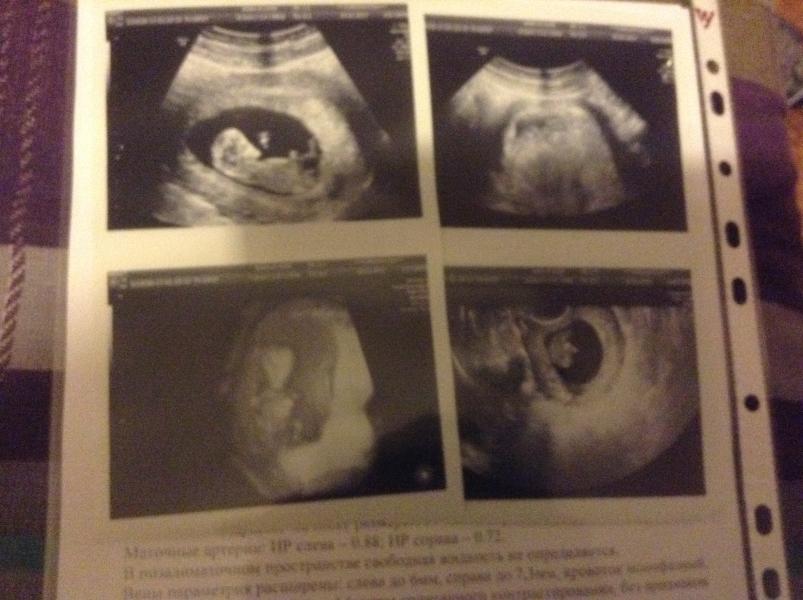

Вчера была на УЗИ у Якубовой в 9 месяцев. Понравилось все, приятная женщина, были на приеме с мужем все показала, рассказала. Перекрытие зева на 14 мм у меня так и осталось, как и отслойка 30 мм на 3,5 мм. Надеюсь, что поднимется со временем. Кровь идёт каждый день. Немного, но настроение каждый раз падает. Плюс в пн отправляют на работу, так как на больничном больше месяца. Очень боюсь работать в таком состоянии. Думаю выйти на 1 день и ложится тогда опять в больницу. Кто как переживал это состояние?

@alevanna, я на работу и не рвусь, каждый раз говорю, что у меня кровь и прошу меня оставить, мне дают убойную дозу транексама, кровь останавливается на пару дней и они со спокойной совестью выписывают. На УЗИ написали что отслойка у меня 14 мм, а это не правда. Якубова вчера 30 мм поставила. И у меня всех в палате так выписали. На больничном я с 21 декабря.